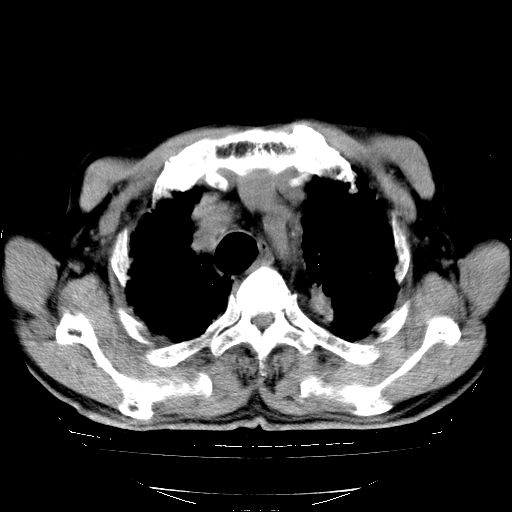

标题: CT25149:男,69岁,反复咳嗽、咳痰五年余,呼吸困难三天。 [打印本页]

男,69岁,反复咳嗽、咳痰五年余,呼吸困难三天。

慢支伴感染、肺气肿、肺心病

慢支伴感染、肺气肿、肺心病。双肺间质性改变(间质纤维化)。